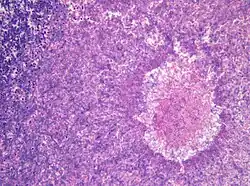

Wachsen eingeatmete Aspergillus-Sporen in der Lunge aus und sind nicht auf eine kompakte Kolonie beschränkt, entwickelt sich eine akute Aspergillose. In der Lunge bilden sich Hyphen und anschließend Myzel, das schließlich über die Blutbahn im gesamten Körper streut. Es bilden sich Metastasen an den Organen und im zentralen Nervensystem. Bei erwachsenen Menschen mit intaktem Immunsystem kommen akute Aspergillosen nicht vor, bei Kindern sind sie sehr selten. Immunsupprimierte Patienten, zum Beispiel nach einer Knochenmark- oder Stammzelltransplantation oder AIDS-Patienten erkranken aber nicht selten daran. Die invasive Aspergillose ist eine gefährliche Infektion mit einer hohen Letalität im Bereich zwischen 50 % und 95 %.[17] Vor allem Vögel erkranken häufig an akuten Aspergillosen. Bei Küken von Haushühnern wird die Erkrankung Aspergillus-Pneumonie genannt und führt immer wieder zu Massensterben in Zuchtanlagen. Auch bei Wildvögeln treten immer wieder Epidemien auf und wurden unter anderem bei Afrikanischen Straußen (Struthio camelus) und Silbermöwen (Larus argentatus) beobachtet. Bei Papageien (Psittaciformes) treten durch Aspergillus verursachte Lungen- und Luftsackmykosen auf.[18] Unter Säugetieren sind Erkrankungen bei Lämmern häufig, bei Hausrind-Kälbern dagegen sehr selten. Epidemien traten bei Kaninchen und Meerschweinchen (Caviidae) auf. Bei Pferden (Equus) sind vor allem Luftsackmykosen gefürchtet. Diese werden zumeist durch Aspergillus fumigatus, aber auch durch andere Aspergilli oder Pilze der Gattungen Penicillium oder Mucor verursacht.[19]